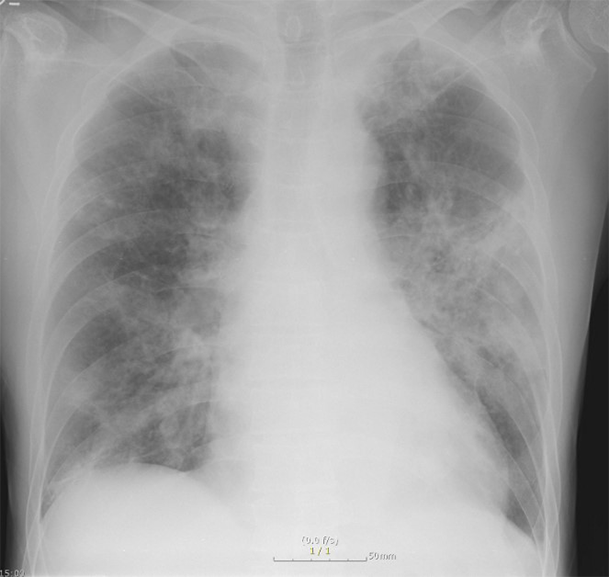

환자의 임상 증상 문진과 진찰 후, 흉부 X선 검사 및 흉부 CT가 진단에 도움이 됩니다.

• 폐결핵 비결핵성항상균 폐질환

img img

그림: 폐결핵과 비결핵성항산균 폐질환의 흉부엑스레이 사진과 흉부전산화단층활영 사진

비결핵성항산균 폐질환은 폐결핵과 비교하였을 때 서서히 진행하거나 변하지 않을 수 있으며, 만성적인 경과를 보이고, 진단이 늦어지는 경향이 있습니다. 두 질환은 모두 환자의 객담을 통한 객담 항산균 도말검사, 객담 항산균 배양 검사를 진행합니다. 객담 배양이 되기 전에는 객담 도말 검사 양성 소견만으로는 결핵균과 비결핵성항산균이 구별이 되지 않으며, 구별을 위해서 결핵균 핵산증폭검사(TB-PCR) 검사를 시행합니다.